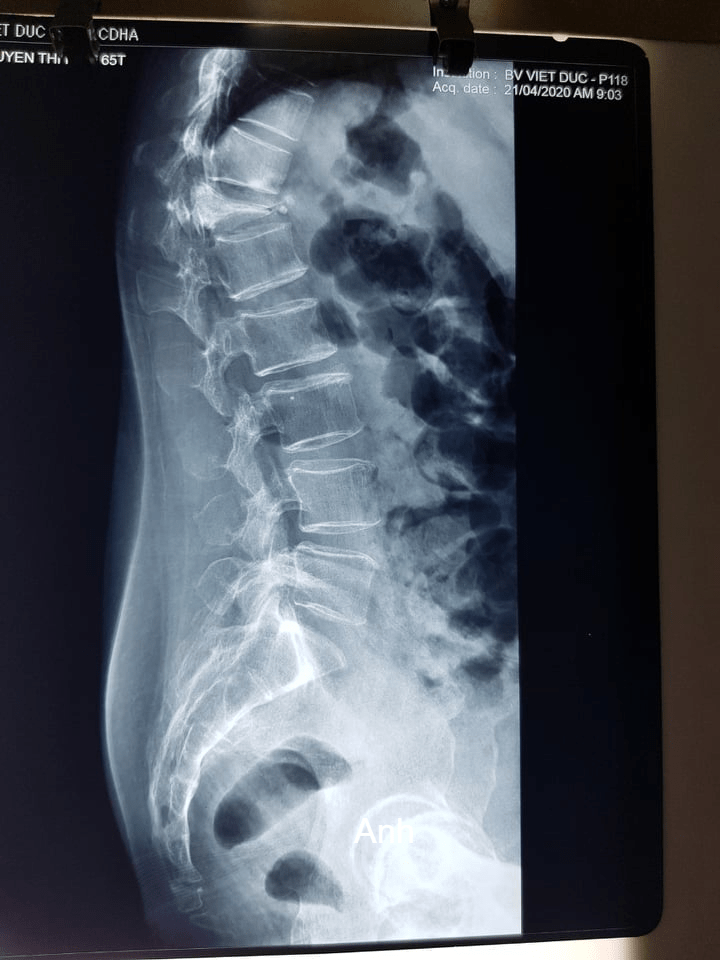

Bệnh nhân Nguyễn Thị NG 64 tuổi bị chấn thương vùng cột sống ngực nhiều tháng nay, sau chấn thương bệnh nhân đau nhiều vùng cột sống nhưng không đi khám và điều trị. Thời gian gần đây bệnh nhân đau nhiều, đau ngày càng tăng, yếu hai chân, gù cột sống, đi lại khó khăn, rối loạn cảm giác vùng bẹn, đùi. Bệnh nhân đến khám tại bệnh viện đa khoa Sơn Tây được khám và chụp phim XQ, cộng hưởng từ phát hiện bị vỡ xẹp nặng thân đốt sống ngực T 12, có mảnh xương vỡ từ thân đốt sống chèn vào tủy sống. Kíp phẫu thuật của Bệnh viện đa khoa Sơn Tây đã hội chẩn với chuyên gia về phẫu thuật cốt sống BS.Phan Minh Trung (Bệnh viện Thanh Nhàn). Bệnh nhân đã được phẫu thuật kết hợp xương nẹp vít thân đốt sống mở cung sau giải ép thần kinh. Ca phẫu thuật thành công, sau mổ bệnh nhân hết rối loạn cảm giác vùng bẹn đùi, hai chân đỡ yếu và sẽ phục hồi theo thời gian, chụp XQ hết gù cột sống.